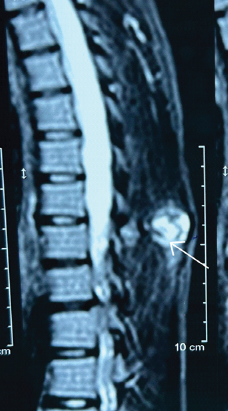

Osteochondroma of Dorsal Spine: A Rare Clinical Entity

Ankit Kumar , Mahendra Tak , Rishita Gehlot , Mukesh Saini

………………………………p.19-22